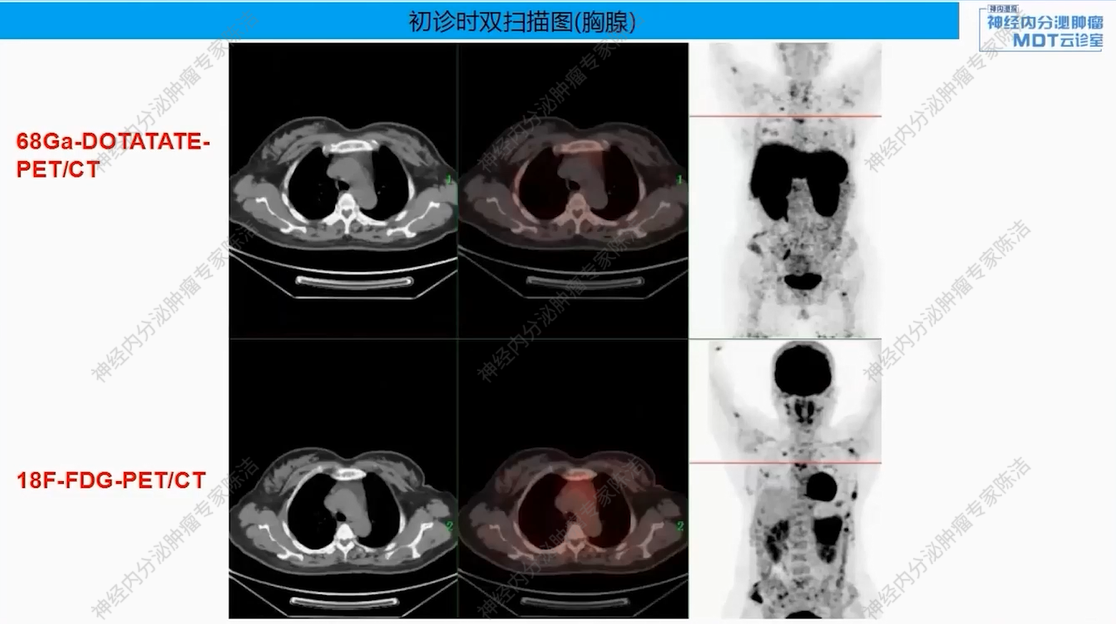

18F-FDG-PET-CT提示:胰尾部见巨大肿物(约8.6*7.2*7.8 cm),FDG代谢明显增高。胰体部另见一小结节(约0.8*0.7 cm),FDG代谢轻度增高。全身多发骨质改变,FDG代谢增高。

68Ga-DOTANOC-PET-CT提示:胰尾部巨大肿块,DOTANOC摄取阴性;胰体部小结节,DOTANOC摄取阳性。甲状旁腺区多发结节,DOTANOC摄取阳性;垂体区稍增大,DOTANOC摄取阳性。

核医学科徐俊彦教授:本病例双扫描PET显像体现了该患者多发肿瘤间异质性。胰尾大病灶(胰岛素瘤)呈SSTR阴性、FDG阳性,这符合约50%胰岛素瘤不表达SSTR的特征。而胰体小病灶呈SSTR阳性、FDG轻度增高。垂体区在SSTR(有生理性摄取)和FDG(无生理性摄取)上均呈阳性,提示垂体瘤可能。骨骼病灶呈SSTR和FDG“双阳性”,高度提示为SSTR阳性的NET转移,但建议对于骨病灶,可对相对表浅的病灶行骨穿以进一步明确骨病灶情况。从最初影像可见髂骨存在明显骨质破坏,甚至骨皮质整体受损,因此骨转移的可能性较大。然而,鉴于该患者同时患有甲状旁腺瘤,甲状旁腺瘤常伴发棕色瘤改变,故目前不能排除甲状旁腺继发的骨改变的可能。

病理科黄丹教授:病理证实了两个胰腺病灶均为G1级NET,但激素表达和SSTR状态不同(胰岛素+/SSTR- vs 胰高血糖素+/SSTR+),印证了该患者胰腺多发NET病灶间的异质性。本病例的一个关键点在于,胰尾的巨大胰岛素瘤虽然FDG代谢活跃,但其Ki-67指数低(约1%)。这种FDG高代谢与Ki-67低表达的不一致现象在临床上虽罕见,但确实存在。这提示该肿瘤可能存在特殊的生物学行为,需密切随访。

该患者以低血糖为首发症状,影像学发现胰腺占位、甲状旁腺及垂体病变,并检测到MEN1胚系基因大片段缺失而最终确诊。胰腺上同时存在SSTR阴性的胰岛素瘤和SSTR阳性的神经内分泌肿瘤,且骨转移灶(SSTR阳性)极可能来源于后者(胰体小病灶),而非引起主要症状的前者(胰尾大病灶)。